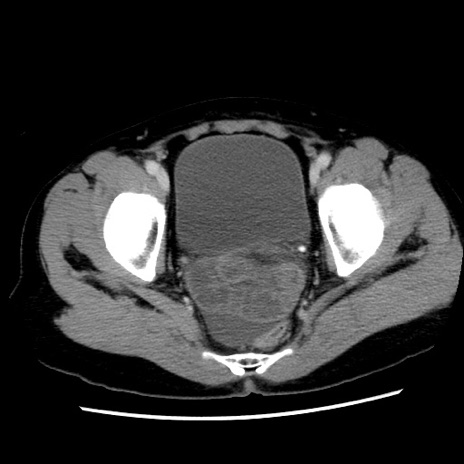

症例10(横断像)

【症例】 50歳代女性

【主訴】 腹痛

【現病歴】前日生レバーを食べた。今朝に排便あり。 昼前に突然発症の腹痛を生じ、当院救急外来を受診した。

【既往歴】 子宮筋腫にてで子宮全摘後

【身体所見】 意識清明、腹部:平坦、軟、下腹部やや左を中心に圧痛・反跳痛あり、筋性防御あり

【データ】WBC 7800、CRP 0.07